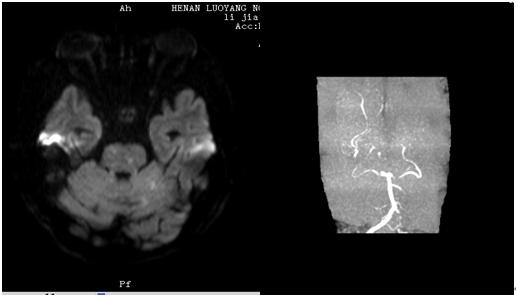

图4 左侧基底节区急性孤立性梗死灶,同侧MCA狭窄(图源 作者提供)